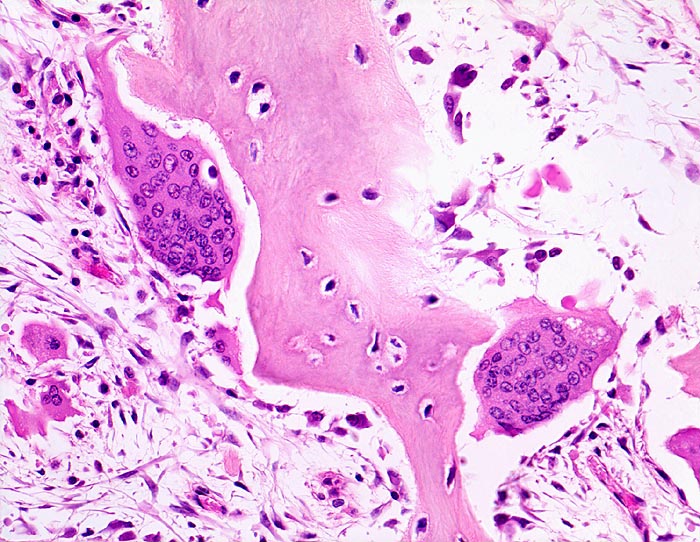

An den betroffenen Stellen ist sowohl der Knochenabbau als auch der Knochenanbau gesteigert. Die Osteoklasten sind auffallend gross und enthalten sehr viele Kerne (> 3518). Die aktivierten Osteoblasten produzieren verdickte und grob geflochtene Spongiosabälkchen. Der neugebildete Knochen ist strukturell und morphologisch abnorm und schlecht mineralisiert. Der Knochen wird dadurch weich und anfällig auf Frakturen oder Deformation unter Belastung (nach vorne gebogene Säbelscheidentibia). Das Knochenmark wird ersetzt durch fibrovaskuläres lockeres Stroma, welches an Granulationsgewebe erinnert. Mikroskopisch werden eine osteolytische Initialphase, eine Umbauphase mit verstärkter Knochenneubildung und eine sklerosierende Stabilisationsphase mit strukturellem Umbau und Spongiosierung der Kortikalis (verbreiterte spongiosaartige Kortikalis) unterschieden.

• Riesenosteoklasten mit über 20 Kernen sind an der Knochenoberfläche erkennbar.

• Vermehrte kubische aktive Osteoblasten bauen Knochen an.